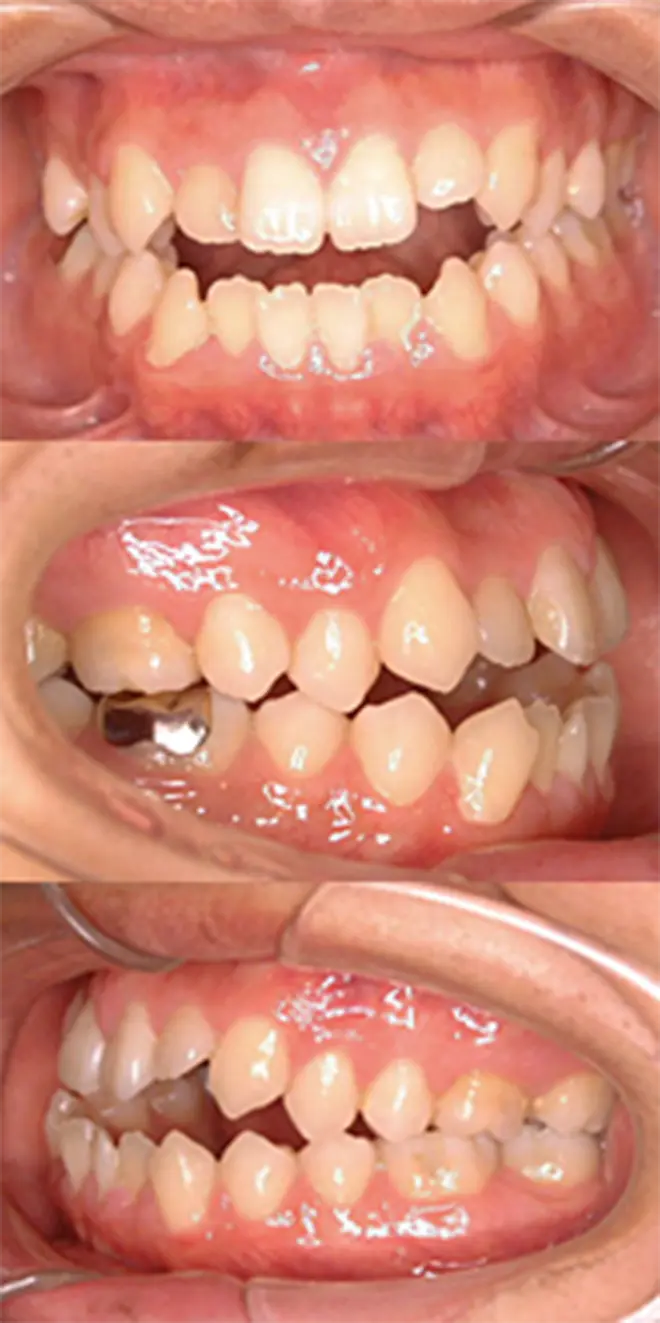

矯正歯科治療後、あらためて当院を受診されました。口元の突出感の改善とガミースマイルの治療を行ないました。

すでに上下左右の4本が抜歯されていたので、口元の突出感がある程度残ってしまっています。上下の唇の重なる位置と、上の前歯の先端の位置関係の変化が見られます。

| 患者さまの年齢・性別 | 20代・女性 |

|---|---|

| 治療期間 | 2年 |

| 治療費(税込) | 880,000円 |

| 主訴 | 口元の突出感が気になる。 |

| 診断名・主な症状 | 上下顎前突 |

| 治療に用いた主な装置 | セルフライゲーションブラケット装置(デイモンシステム)、歯科矯正用アンカースクリュー |

| 治療内容 |

すでに矯正治療を受けたあとだったため、当院では口元の突出感の改善とガミースマイルの治療を行ないました。 |

| 抜歯部位 | 非抜歯 |